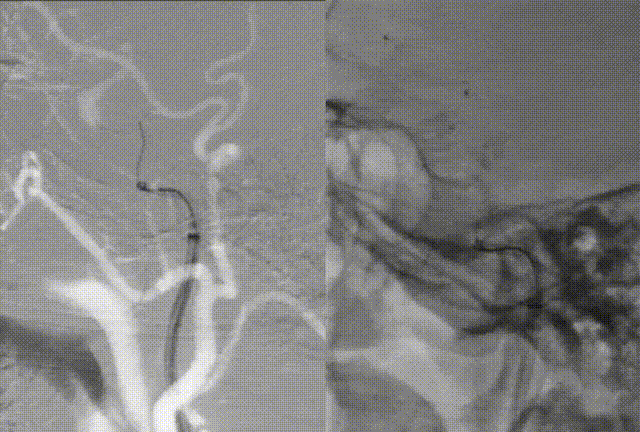

Right femoral artery access was obtained, and an 8F femoral sheath was inserted. Angiography revealed complete occlusion of the right ICA from the C1 segment to the intracranial portion. Collateral circulation to the right ICA territory was provided via the ophthalmic artery from the right external carotid artery. The anterior communicating artery was not visualized. The vertebral artery supplied the ICA territory through the posterior communicating artery.

A coaxial system composed of a glidewire, a 125 cm MPA1 catheter, and a 6F 90 cm sheath was advanced into the right common carotid artery. The long sheath was positioned at the proximal bifurcation of the right CCA. The occlusion was crossed using the glidewire and MPA1 catheter, followed by advancement of the 6F 115 cm Zenith Distal Access Catheter through the occlusion.